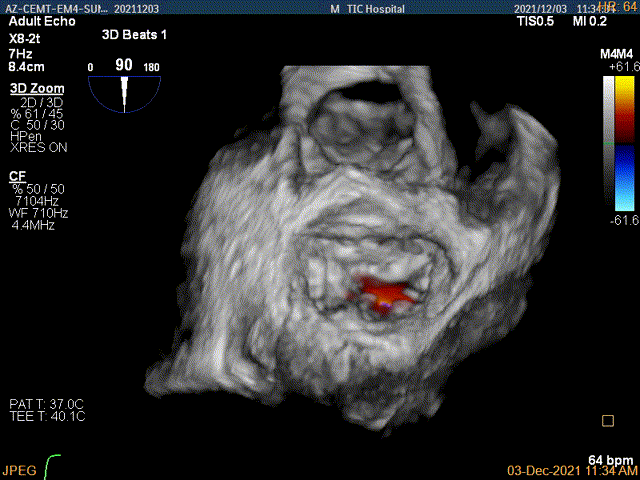

3D-color MV view:大量反流,起源于1区

3D证实夹子AC区残余脱垂被禁锢住

3D-color证实无明确残余分流